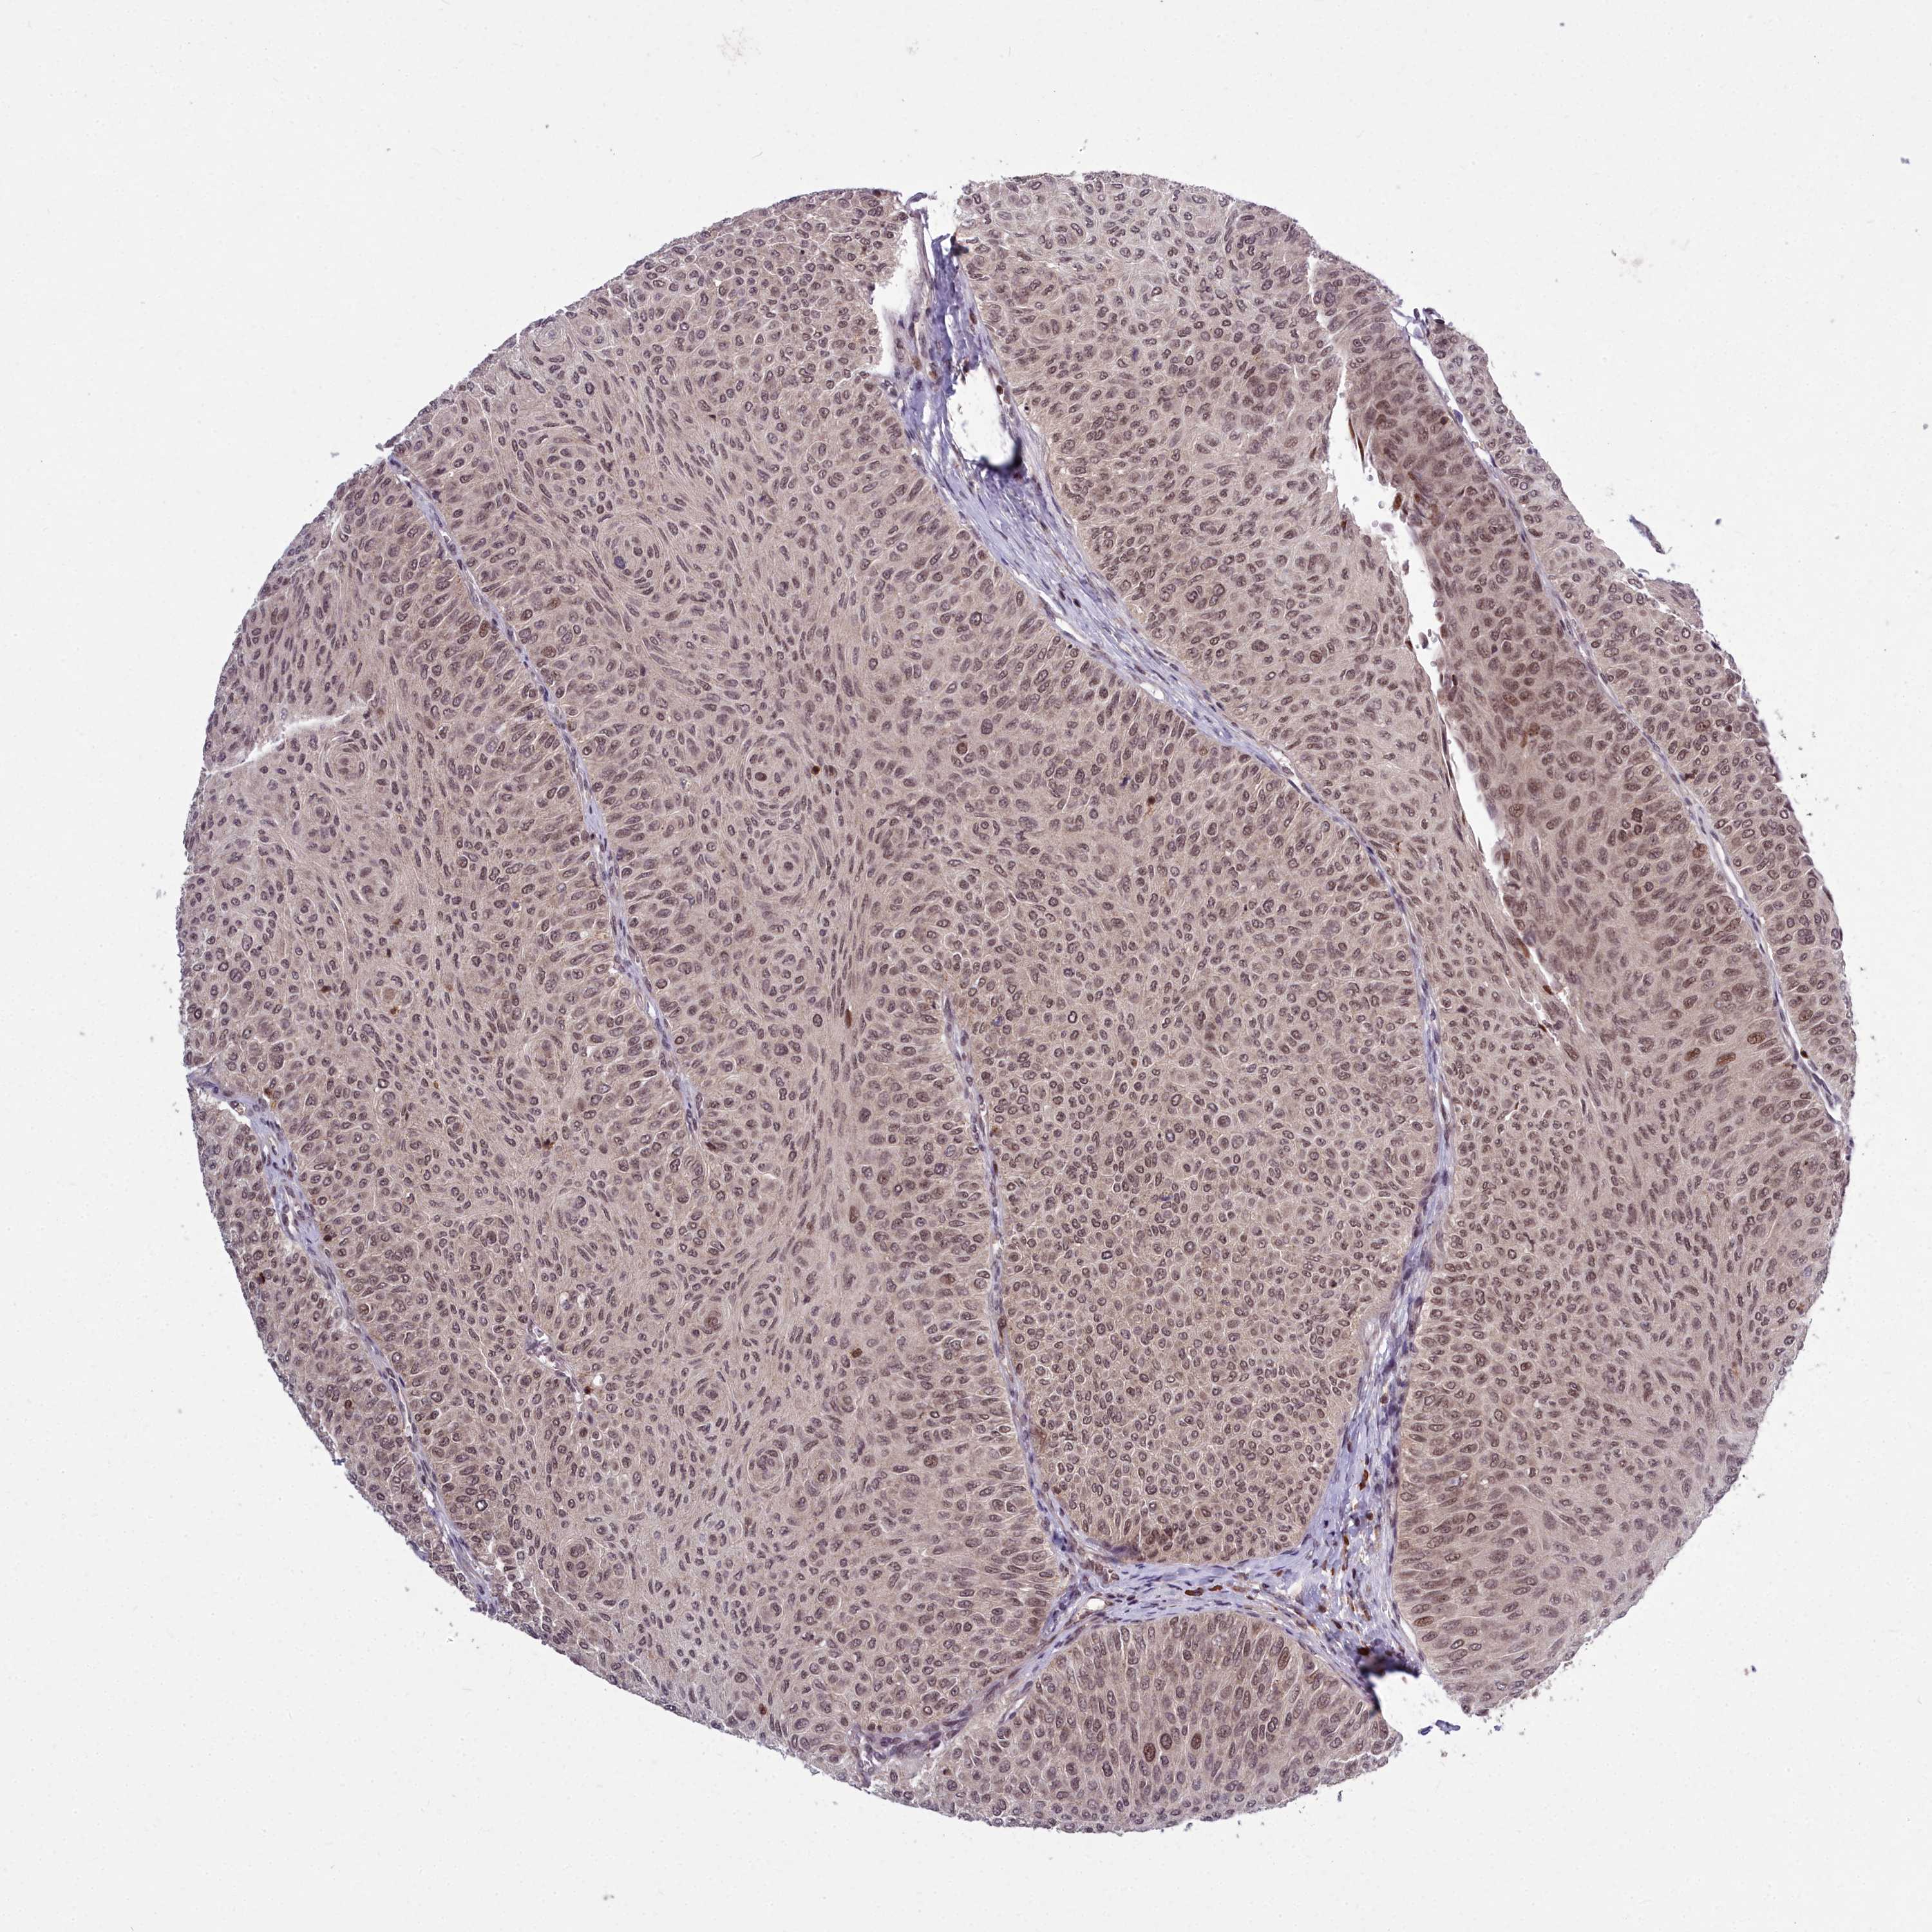

UROTHELIAL CANCER - Protein expressioni

A mouse-over function shows sample information and annotation data. Click on an image to view it in a full screen mode. Samples can be filtered based on level of antibody staining by selecting one or several of the following categories: high, medium, low and not detected. The assay and annotation is described here.

Note that samples used for immunohistochemistry by the Human Protein Atlas do not correspond to samples in the TCGA dataset.

Antibody stainingi

Antibody staining in the annotated cell types in the current human tissue is reported as not detected, low, medium, or high, based on conventional immunohistochemistry profiling in selected tissues. This score is based on the combination of the staining intensity and fraction of stained cells.

Each image is clickable and will lead to virtual microscopy that enables deeper exploration of all samples and also displays staining intensity scores, fraction scores and subcellular localization as well as patient and tissue information for each sample.

Antibody HPA044811

Staining

High

Medium

Low

Not detected

Intensity

Strong

Moderate

Weak

Negative

Quantity

>75%

75%-25%

<25%

None

Location

Nuclear

Cytoplasmic/membranous

Cytoplasmic/membranous,nuclear

Urothelial carcinoma, Low grade

Urothelial carcinoma, High grade